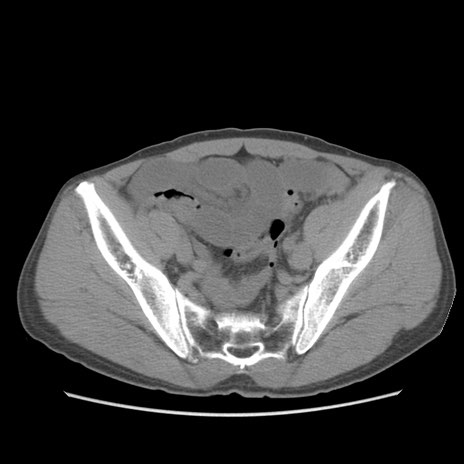

症例56 CT(横断像)